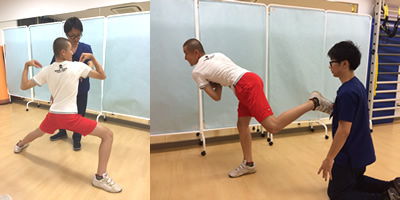

手術後3ヶ月頃のリハビリの様子です。

体幹や肩甲骨周囲のトレーニングを積極的に行ないます。